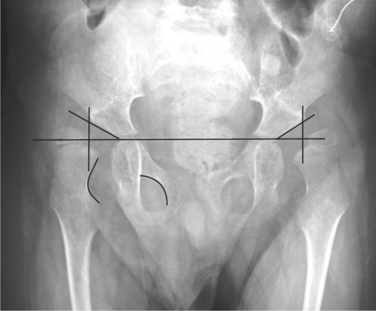

Musculoskeletal problems of altered muscle tone, muscle weakness, and joint restrictions are common and can result in functional and orthopedic impairments. For example, the abnormal pull of the spastic iliopsoas and adductor muscles are the initiating deforming force in hip dislocations (Fig. 35-5).

When spasticity and contracture of the iliopsoas occur, the medial joint capsule is compressed and the femoral head is pushed laterally. As lateral drift of the femoral head occurs, the iliopsoas insertion on the lesser trochan- ter becomes the center of rotation. Acetabular development ceases when the femoral head is completely displaced laterally, and further hip flexion pushes the head posteriorly to complete the dislocation (Fig. 35-6).9

Figure 35-6 Anteroposterior radiograph of a young child with spastic quadriplegia and subsequent hip dysplasia with subluxation on the left. Note that a line drawn vertically down from the outermost edge of the acetabulum would bisect the head of the femur. Failure of the acetabulum to deepen with weight bearing resulting in hip dysplasia and subluxation occur as a result of the inability to weight bear and abnormal muscular forces pulling on the bone. The standard measurement for hip dislocation is a migration percentage. This is done by drawing Hilgenreiner’s line, which provides a horizontal reference to the pelvis and then drawing Perkin’s line perpendicular to Hilgenreiner’s line from the outermost edge of the acetabulum. (Courtesy Allan Glanzman, Children’s Seashore House of the Children’s Hospital of Philadelphia, PA.)